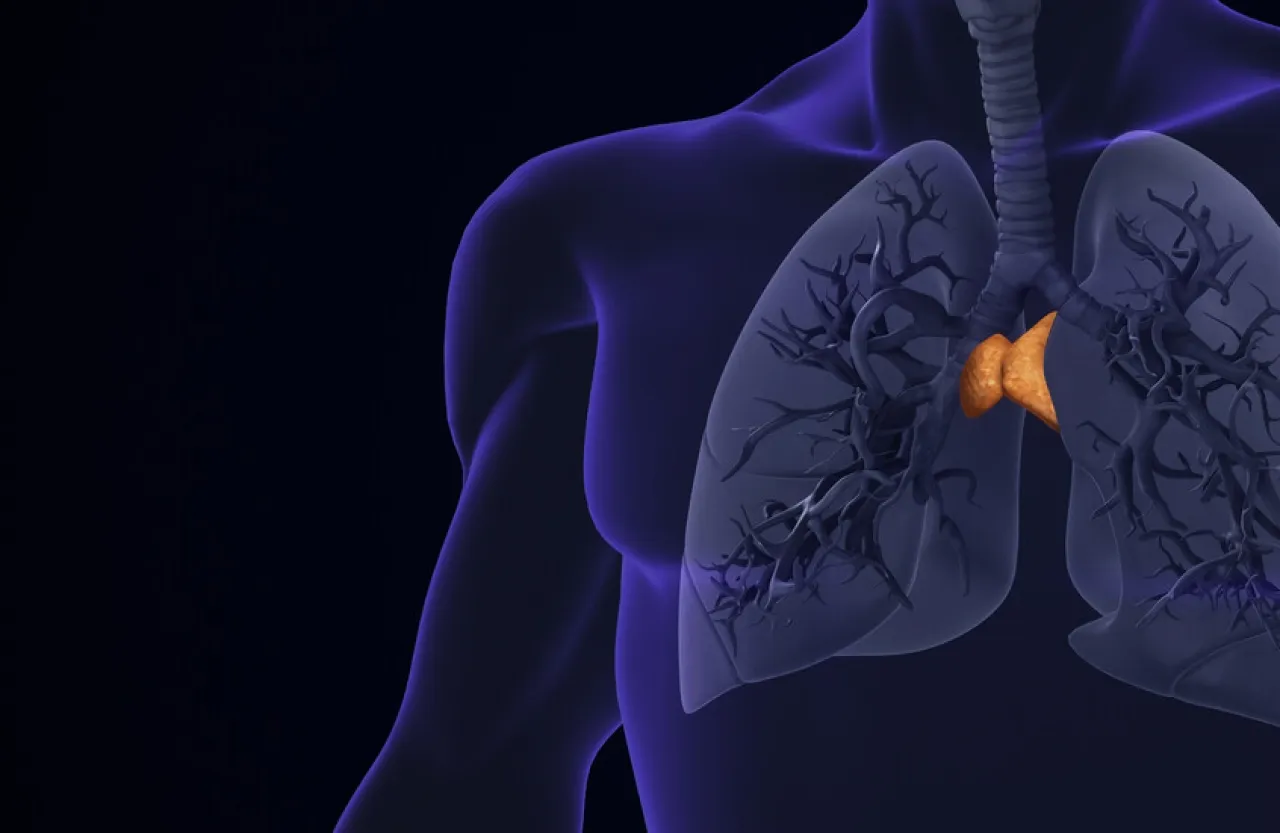

خبرني - كشفت أبحاث جديدة أن غدة صغيرة تعرف باسم "الغدة الزعترية"، كان يعتقد سابقا أنها تفقد أهميتها بعد الطفولة، قد تلعب دورا محوريا في إطالة العمر وتعزيز صحة جهاز المناعة لدى البالغين.

وتقع الغدة الزعترية، أو كما تعرف أيضا باسم "الغدة التيموسية" (Thymus)، خلف عظمة القص، وتشبه "ميدان تدريب" للخلايا التائية (T cells) المناعية التي تساعد الجسم على التعرف على العدوى ومكافحتها.

ورغم أنها تتقلص مع العمر وتنتج عددا أقل من هذه الخلايا بعد البلوغ، ما جعل العلماء يتجاهلون دورها في صحة البالغين لعقود، إلا أن دراستين حديثتين نشرتهما مجلة Nature تقلبان هذه الفكرة رأسا على عقب.

ففي الدراسة الأولى، حلل باحثون من "ماساتشوستس جنرال بريغهام" بيانات أكثر من 25 ألف شخص شاركوا في برنامج وطني لفحص سرطان الرئة، بالإضافة إلى أكثر من 2500 مشارك في دراسة "فرامنغهام للقلب".

وباستخدام الذكاء الاصطناعي لمراجعة صور الأشعة المقطعية، قام الباحثون بتقييم حجم وبنية وتكوين الغدة الصعترية لكل مشارك، ما أنتج "درجة صحة الغدة الزعترية".

وكانت النتائج لافتة: الأشخاص الذين تمتعوا بغدة زعترية أكثر صحة كانوا أقل عرضة للوفاة بنسبة 50% تقريبا، وأقل عرضة للوفاة بسبب أمراض القلب بنسبة 63%، وأقل عرضة للإصابة بسرطان الرئة بنسبة 36%، مقارنة بذوي الدرجات المنخفضة. واستمرت هذه النتائج حتى بعد احتساب عوامل العمر والمشاكل الصحية الأخرى.

أما الدراسة الثانية، فراجعت بيانات 1200 مريض بالسرطان عولجوا بالعلاج المناعي (أسلوب يعتمد على تحفيز جهاز المناعة لمحاربة الخلايا السرطانية). وتبين أن المرضى الذين يتمتعون بصحة أفضل للغدة الزعترية كانوا أقل عرضة لتطور السرطان بنسبة 37%، وأقل عرضة للوفاة بنسبة 44%، بغض النظر عن اختلافات المرضى والأورام والعلاجات.

ويشرح الباحثون أن تدهور وظيفة الغدة الزعترية يجعل جهاز المناعة أقل قدرة على مواجهة التهديدات الجديدة مثل السرطان. كما ربطوا بين ضعف صحة الغدة وعوامل مثل الالتهاب المزمن والتدخين وارتفاع الوزن.

وقال هوغو إيرتس، أحد مؤلفي الدراسة: "لقد تم التغاضي عن الغدة الزعترية لعقود، وقد تكون القطعة المفقودة في تفسير سبب تقدم الناس في العمر بشكل مختلف، ولماذا تفشل علاجات السرطان لدى بعض المرضى". وأضاف أن هذه النتائج تستدعي اهتماما أكبر بصحة الغدة، وقد تفتح آفاقا جديدة لحماية جهاز المناعة مع التقدم في العمر.

ورغم هذه النتائج الواعدة، يؤكد العلماء الحاجة إلى مزيد من الدراسات لتأكيد هذه الاكتشافات، معربين عن أملهم في أن يساعد تحسين فهم صحة الغدة الزعترية الأطباء على تقييم مخاطر الأمراض بشكل أفضل وتوجيه قرارات العلاج.